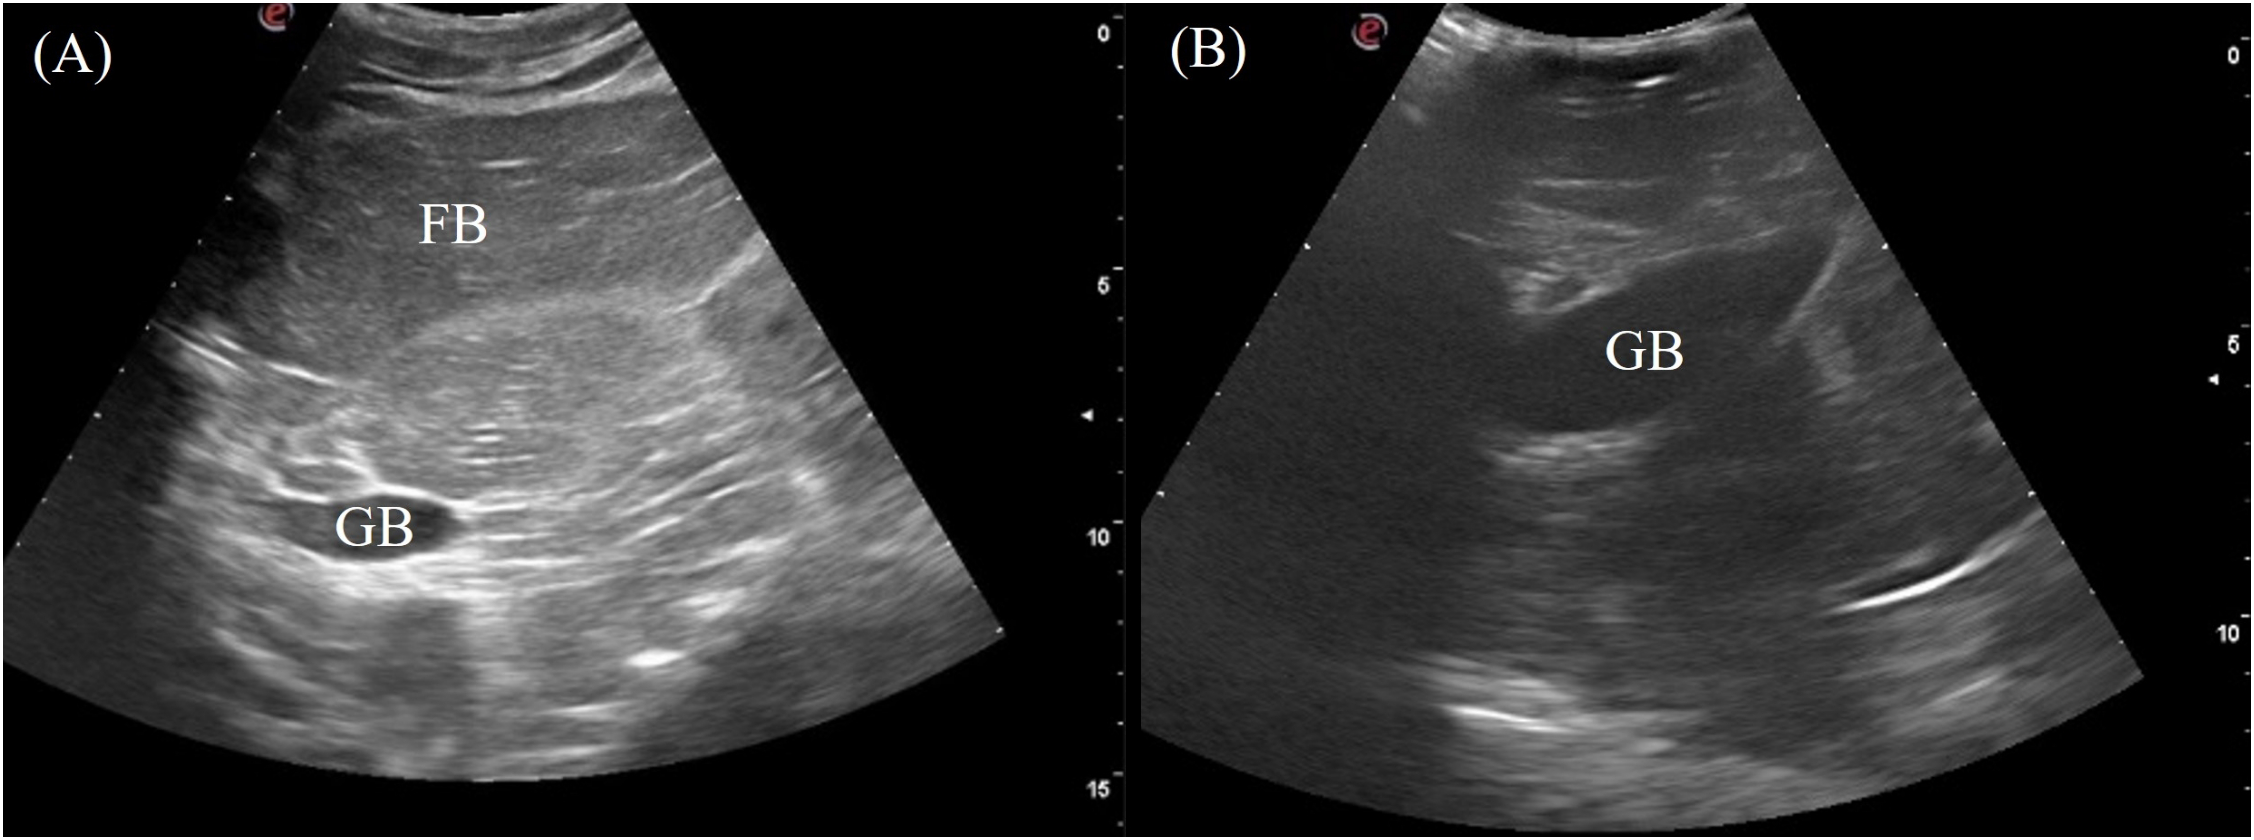

3.3.3 Gallbladder

The gallbladder was a fluid-filled sac located ventromedially caudal to the right liver lobe. It was visualized in 6/7 of the crocodilians except for the saltwater crocodile. The transducer was placed on the mid-portion of the right flank and directed ventrally, using the fat body as an acoustic window (Figure 3, transducer position 7). It was also visible ventrally if not obstructed by the osteoderms (Figure 3, transducer position 13). The gallbladder was visualized as an irregular globular structure with a thin hyperechoic wall filled with hypoechoic to anechoic content (Figure 7).

Figure 7

Ultrasonographic appearance of the gallbladder in sagittal via the (A) right lateral view in Alligator sinensis and (B) the ventral view in Tomistoma schlegelii. [FB, fat body; GB, gallbladder].